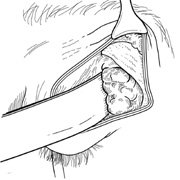

wall still can be carried out. | Fig. 9. A,B. Coronal and axial CT images of a large intraconal neoplasm. C. Because it was felt to represent a well-encapsulated cavernous hemangioma, this

lesion was a candidate for removal via an eyelid crease orbitotomy

without bone removal. The eyelid crease incision marked. D. Incision made with scalpel. E. Orbicularis muscle is tented up and incised to expose the underlying septum. F. Dissection of a skin-muscle flap deep to orbicularis exposes the orbital

septum and superior orbital bony rim. G. Cutting cautery is used to incise periosteum along the superior and lateral

rims; finger palpation of the bone helps to direct this incision. H. Periorbita is elevated along the mesial surface of the lateral orbital

rim in order to expose the deep orbital tissues. I. The cavernous hemangioma is visualized in the wound. Retraction is provided

by one or more malleable retractors. J. Cryoprobe is affixed to the hemangioma to facilitate manipulation of the

lesion. K. Large cavernous hemangioma after removal through the eyelid crease incision

which was accomplished without bone removal. L. Periorbita is reattached over the lateral rim. M. The eyelid crease incision is closed with a running suture. |